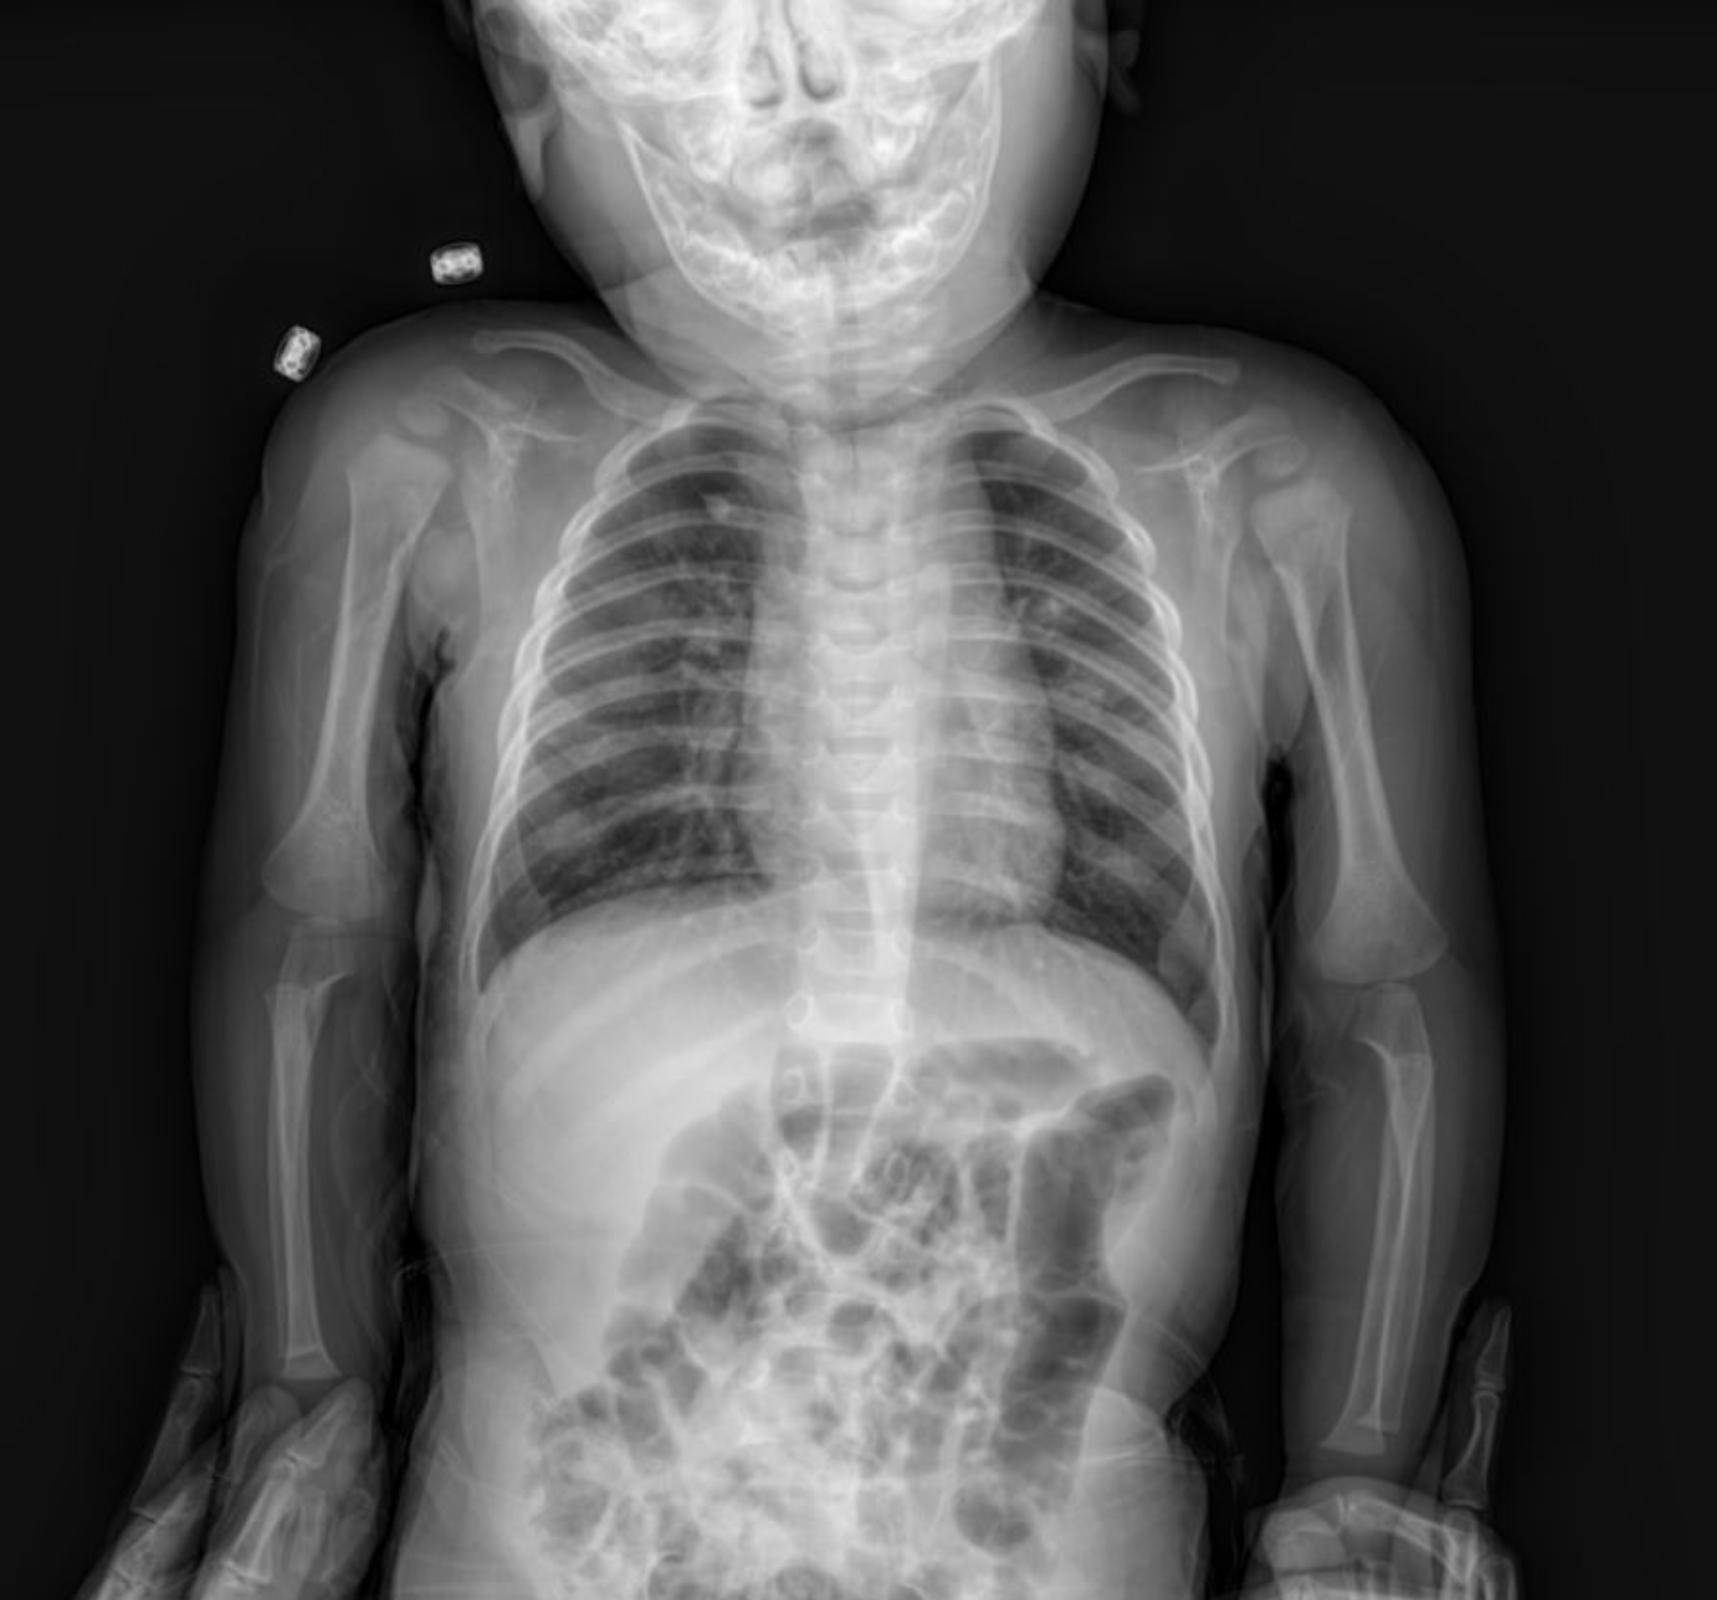

The provided anterior-posterior (AP) chest X-ray of the infant reveals several key features:

- Lungs: The lung fields appear adequately inflated. There is evidence of increased bronchovascular markings, particularly in the perihilar regions, which can suggest bronchial wall thickening or fluid accumulation. Additionally, subtle paracardial infiltration is noted, indicating a mild inflammatory or infectious process adjacent to the heart borders.

- Heart: The cardiac silhouette appears within normal limits for size and contour for a pediatric patient, without overt cardiomegaly. The paracardial infiltration, while present, does not appear to significantly distort the cardiac borders.

- Diaphragm: The diaphragmatic contours are clear and sharp, with no evidence of pleural effusions.

- Bony Thorax: The ribs and clavicles appear intact with no obvious fractures or deformities. The skeletal structures are appropriate for the child’s age.

- Trachea: The trachea appears patent and centrally located.

- Foreign Bodies: Two metallic densities are noted projected over the left upper chest/shoulder region. These would need clinical correlation to determine their nature (e.g., external artifacts, monitoring leads).

Given the clinical presentation of rhonchi and rales, combined with the X-ray findings of increased bronchovascular markings and mild paracardial infiltration, the overall picture is strongly suggestive of a lower respiratory tract infection, such as bronchiolitis or pneumonia, common in infants. The paracardial infiltration further supports an inflammatory process within the lung parenchyma in this region.